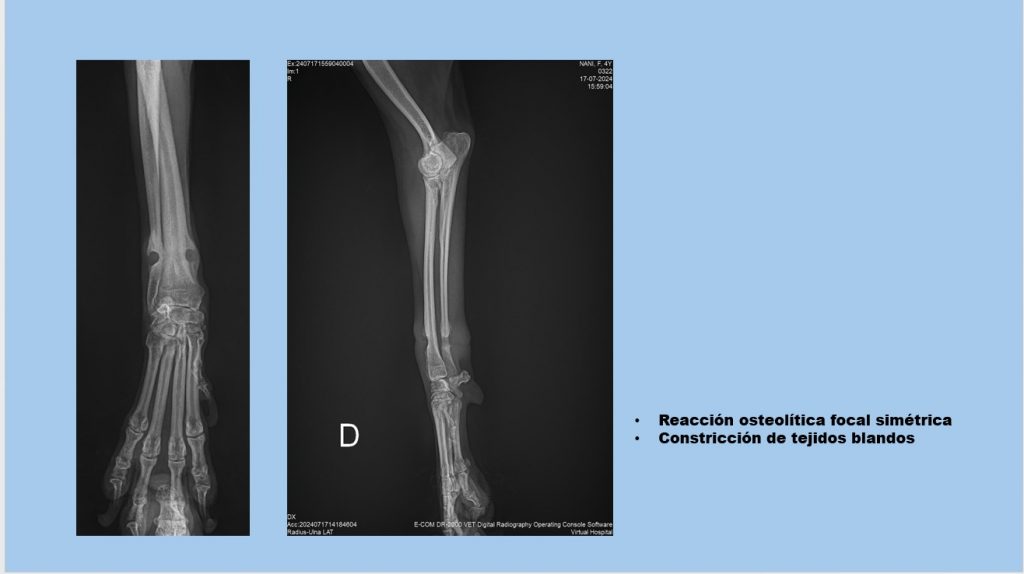

“Es un caso muy peculiar, realmente hay muy pocos reportes, sobre todo en español; por lo general, los reportes que encontré de este tipo de casos son de la India o algunos de Estados Unidos. Básicamente es cuando a un perro o algún gato, también, se le llega a encarnar una liga en su pata o en su cola y esta llega a penetrar hasta el hueso y la piel recubre nuevamente esta liga, haciendo que estas dos especies tengan una claudicación o una cojera persistente sin descubrir una causa esencial”, relata Diana.

Comparte que, al ver las lesiones en el hueso, lo asoció “principalmente a una reacción infecciosa, una osteomielitis bacteriana, pero al abordar el caso de forma quirúrgica, mi idea principal era tomar una muestra para un cultivo o, en dado caso, si encontrábamos un objeto extraño, retirarlo y fue la presencia de una liga de color naranja que estuvo causando toda la lesión en el hueso; no supimos cómo llegó”.